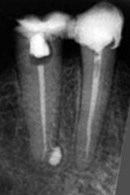

Die linke Aufnahme spiegelt den Erstbefund vom Dezember 99. Auffällig der grosse dunkle Fleck um die Wurzelspitze des mittleren Zahnes, als Resultat des bereits vollzogenen Knochenabbaus. Vermutlich infolge eines, möglicherweise viele Jahre zurückliegenden Traumas, kam es hier wohl zum Abriss der Blutgefässe in Höhe der Wurzelspitze und damit zu einer Unterbrechung der Ernährung des gesamten Pulpen-Gewebes inmitten dieses Zahnes. Nicht mehr ernährtes Gewebe stirb nun mal ab und beginnt sich zu zersetzen.

Manche dieser Zersetzungsprodukte wiederum sind aggressiv genug, um selbst die nächste Runde an Gewebszerstörung einzuleuten. Sich selbst verstärkende Prozesse unterbricht man besser sofort, ganz klar! Nur nicht der Patientin, denn die erschien erst wieder Anfang August 2002 mit leicht geschwollener Oberlippe im Gepäck. Der Rest verlief deutlich konsequenter mit Wurzelfüllung Ende August und Resektion des Gewebes um die Wurzelspitze Mitte September.

Die 2. Aufnahme ist von 2002, die 3. vom 25.06.2010.